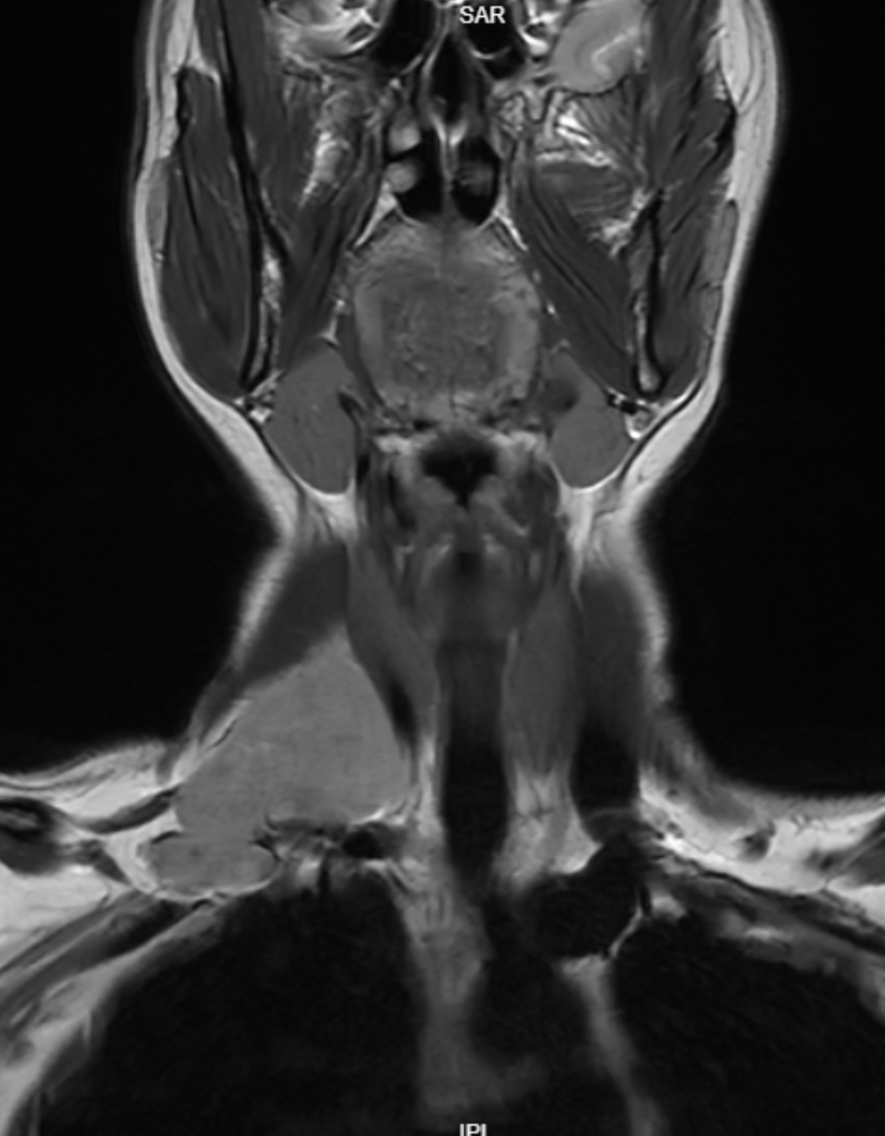

MRI Scan Analysis CT Scan Analysis Temporal Scan Analysis Orbits Scan Analysis MRI Scan Analysis CT Scan Analysis Temporal Scan Analysis Orbits Scan Analysis

Primary Reads & Second Opinions

We do primary reads and second opinions. For collaborating or partnering for primary reads of scans, please connect with us at reach@hnnradiologist.com.

MRI Brain / Spine: ₹1000